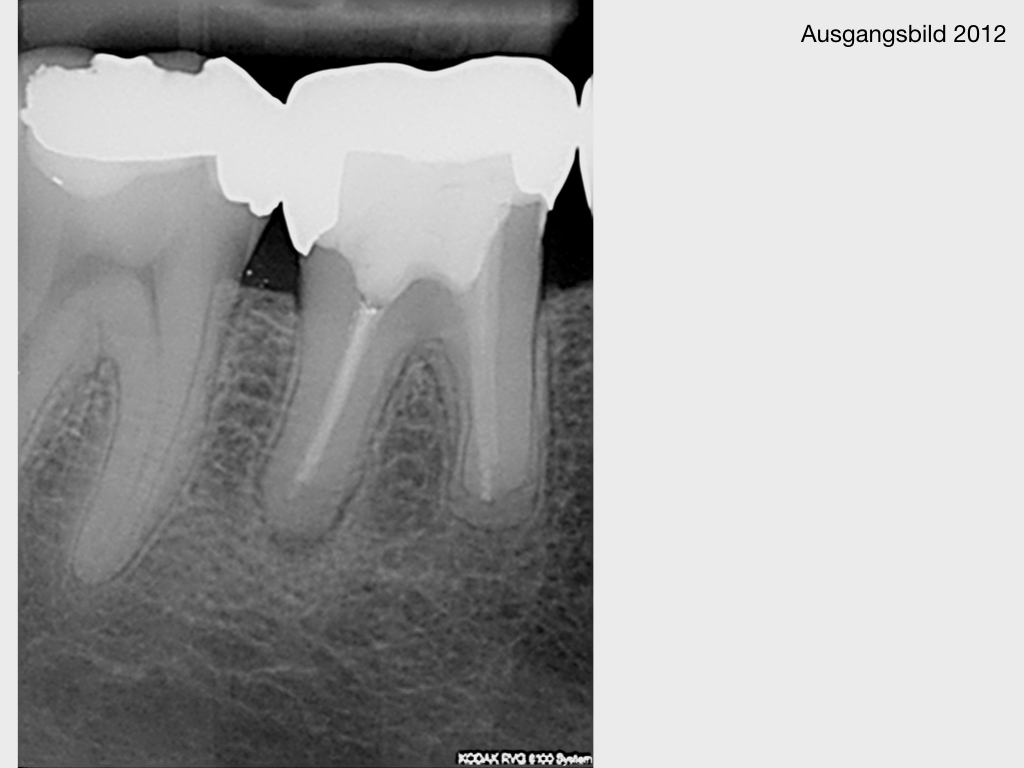

WSR2.010

1024 × 768

Kurz berichtet – Z.n. WSR